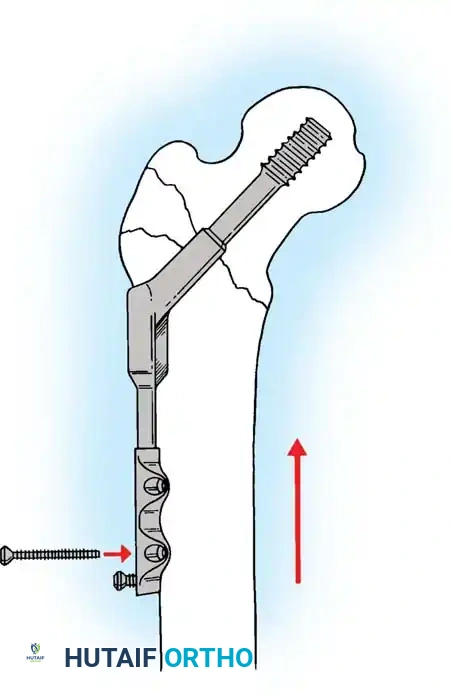

5. Intramedullary Nailing (For Unstable Fractures)

If a cephalomedullary nail is chosen, the entry point is established at the tip of the greater trochanter (or slightly medial, depending on the specific implant design).

Insertion of the cephalomedullary nail down the femoral shaft. Care must be taken not to distract the fracture site during insertion.

After the nail is seated, the proximal lag screw(s) are inserted through the nail into the femoral head, adhering to the same TAD principles.

Proximal locking of the cephalomedullary nail. The targeting guide ensures accurate trajectory into the femoral neck.

Finally, distal locking screws are placed to control rotation and maintain length.